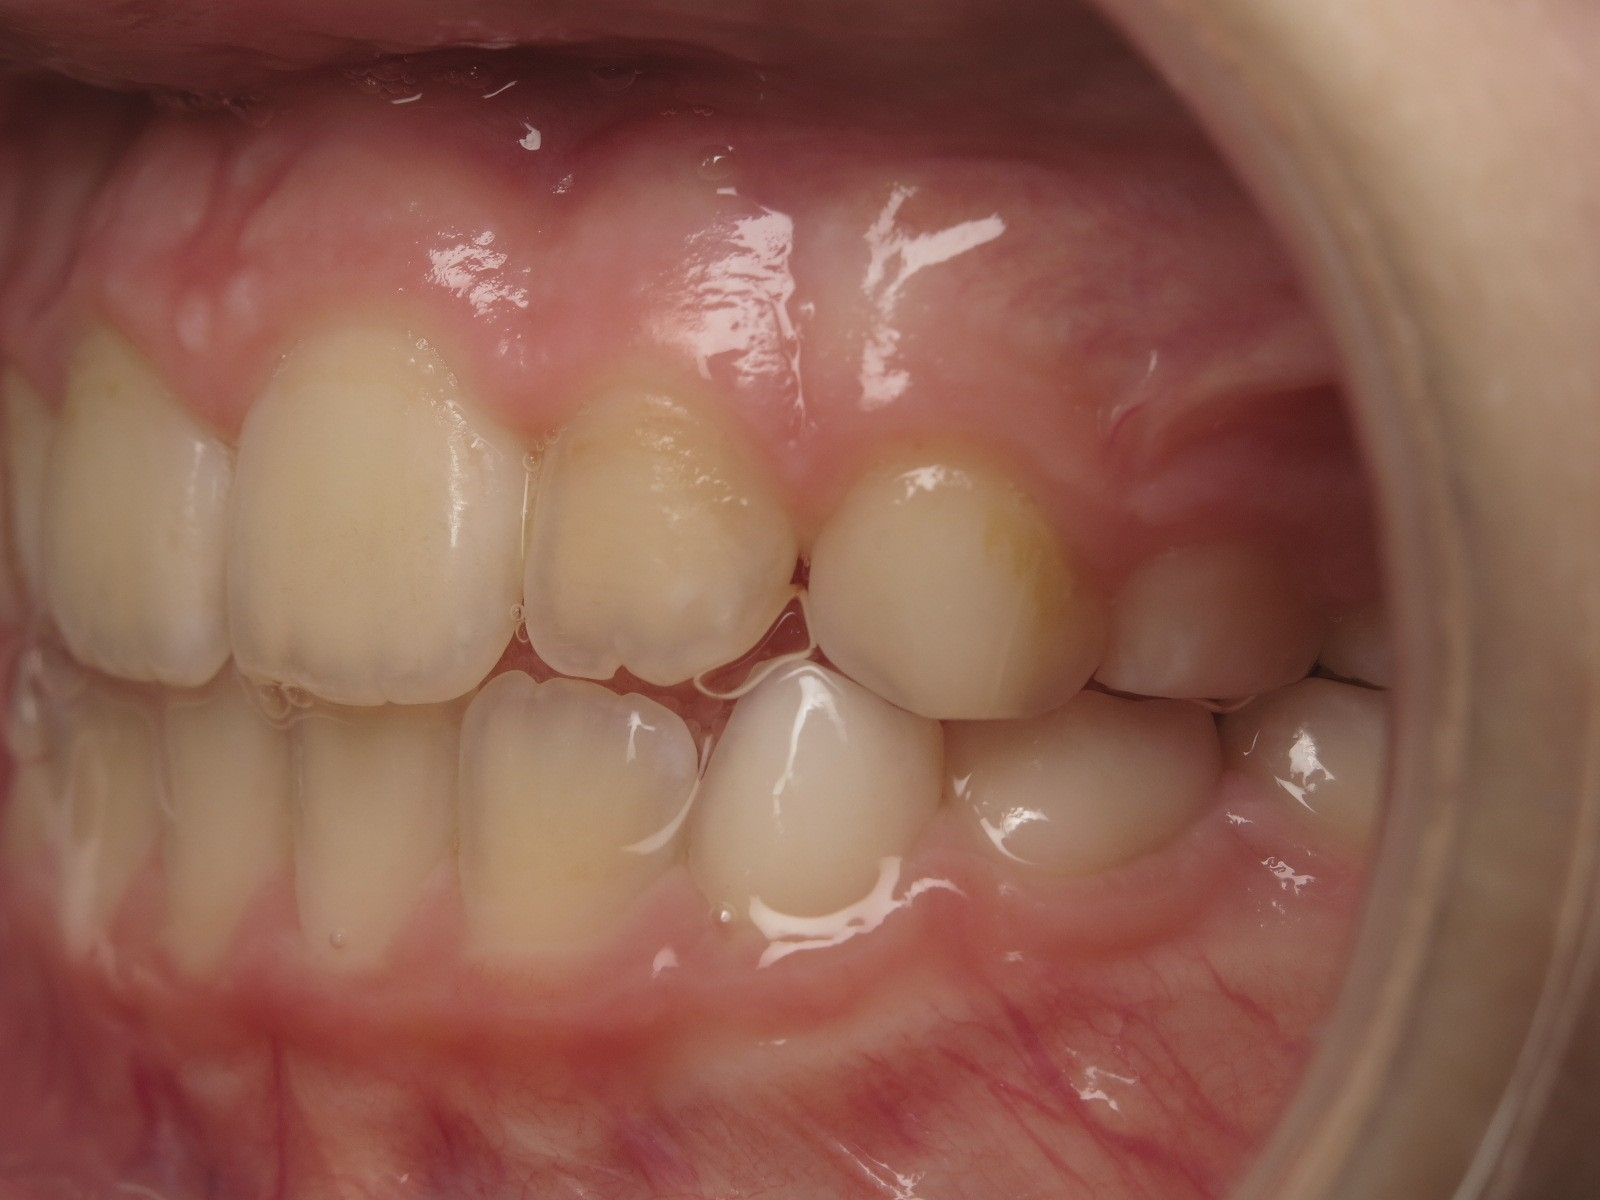

18 béance inversé droit 4 ans

inversion des dents postérieur et espace entre l'arcade du haut et du bas (béance)

bilan de début et en cours de traitement